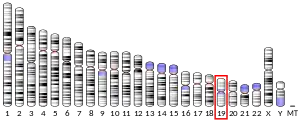

The insulin receptor (IR) is a transmembrane receptor that is activated by insulin, IGF-I, IGF-II and belongs to the large class of receptor tyrosine kinase.[5] Metabolically, the insulin receptor plays a key role in the regulation of glucose homeostasis; a functional process that under degenerate conditions may result in a range of clinical manifestations including diabetes and cancer.[6][7] Insulin signalling controls access to blood glucose in body cells. When insulin falls, especially in those with high insulin sensitivity, body cells begin only to have access to lipids that do not require transport across the membrane. So, in this way, insulin is the key regulator of fat metabolism as well. Biochemically, the insulin receptor is encoded by a single gene INSR, from which alternate splicing during transcription results in either IR-A or IR-B isoforms.[8] Downstream post-translational events of either isoform result in the formation of a proteolytically cleaved α and β subunit, which upon combination are ultimately capable of homo or hetero-dimerisation to produce the ≈320 kDa disulfide-linked transmembrane insulin receptor.[8]